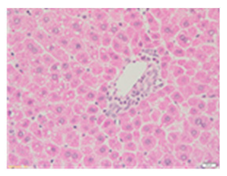

Liver wet weights of all rat groups showed no significant differences (Table 8). According to histochemical hematoxylin and eosin (H&E) staining, treatment with the highest dose of MPE (1000 mg/kg BW) did not result in morphological changes in the liver tissue (B) when compared with DI water treatment (A). Obviously, CCl4 induction (ip)/DI water treatment (po) caused hepatoxicity, which was indicated by a severe degree of fatty changes and fatty cysts in the liver tissue (C), whereas pretreatments of silymarin (100 mg/kg BW, po) effectively decreased the degree of fatty changes and fatty cysts in the liver when compared with the CCl4/DI water group. Indeed, MPE (250 and 1000 mg/kg BW, po) lowered the degree of lipid accumulation in the liver; inversely, MPE (500 mg/kg BW, po) exhibited a severe degree of lipid accumulation. Apparently, taking paracetamol (2 g/kg BW) induced a severe degree of hepatic necrosis when compared with rats that had not received the treatment. Similarly, pretreatments of silymarin (100 mg/kg BW, po) and MPE (250 and 1000 mg/kg BW, po) revealed a mild degree of hepatic necrosis, while MPE (500 mg/kg BW, po) revealed a moderate to severe degree of hepatic necrosis. Accordingly, the findings imply that the consumption of MPE (1000 mg/kg BW) was not harmful to the liver of healthy rats, while MPE (250 mg/kg BW) did improve fat deposition in the livers of CCl4-fed rats and offered protection against liver cell damage in paracetamol-fed rats.

Wet weight values (mean ± SD) and H&E staining of liver from rats with hepatotoxicity induced by CCl4 and paracetamol.